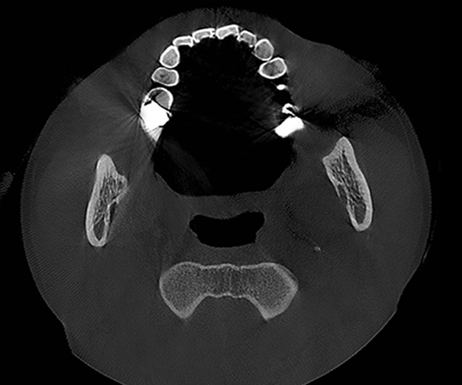

T-MAR Metal Artifact Reduction

T-MAR Metal Artifact Reduction in LargeV Dental CBCT

With the new T-MAR module, the system automatically removes metal artifacts and corrects image distortions intelligently.

Hence, the final images remain clear, accurate, and clinically reliable.